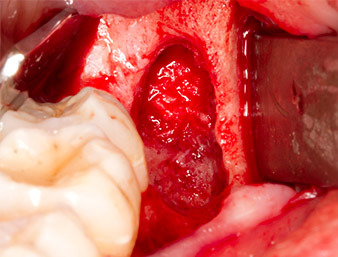

The tissue above the root remnant was not completely ossified and consisted for the most part of granulation tissue modified by inflammation (Fig. 4).

To expose the root remnant with as little trauma as possible to the tissue, a further instrument was used (Piezomed S2) that is primarily indicated for preparing the lateral window in augmentations of the sinus floor. The diamond-coated ball was additionally used to smooth sharp bone edges (Fig. 6 and 7). All the Piezomed attachments were used with the relevant automatic default setting without booster function.